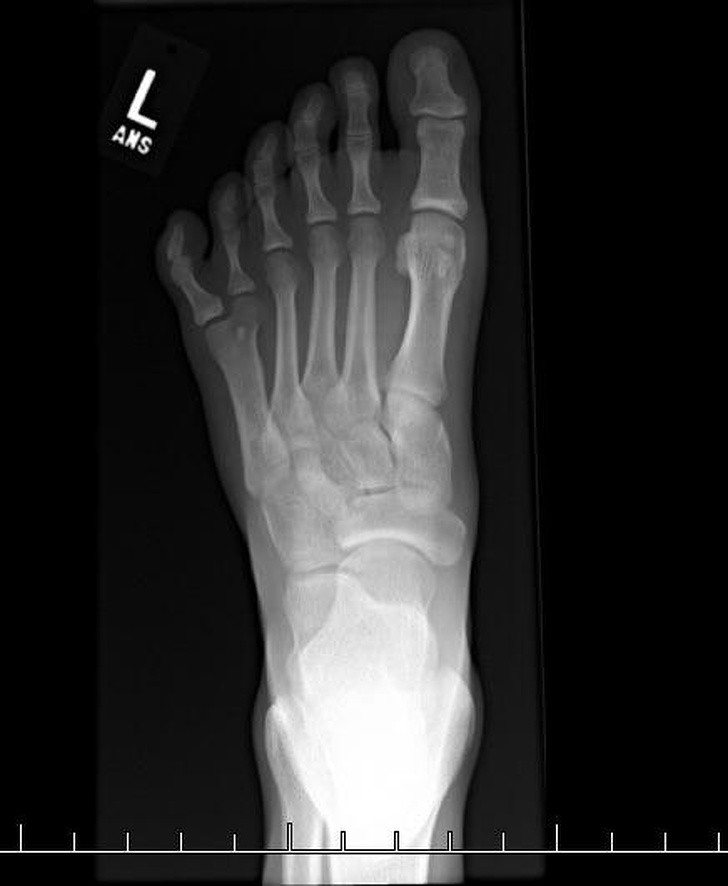

5. Một phim chụp X - quang cho thấy 1 bàn chân 6 ngón.

![]() |

| Ảnh: BrightSide |